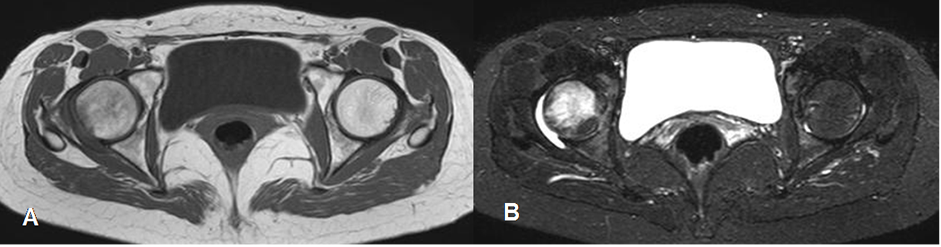

Fig 81. Osteonecrosis.

A: RM axial en T1 y B: RM axial en STIR. Edema óseo inespecífico en la cabeza femoral derecha, hipointenso en T1 e hiperintenso en STIR. Hay escaso derrame asociado.